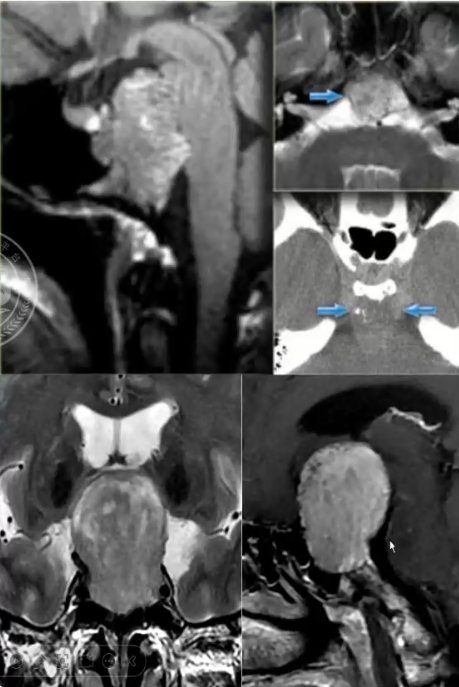

√ 脊索瘤:常见于斜坡,该区域亦是转移瘤、软骨肉瘤的好发部位 垂体常表现正常或向前移位

√ 肿瘤钙化常见

√ 鉴别诊断:软骨瘤与软骨肉瘤。软骨瘤好累及中线区,而软骨肉瘤常发生于偏中线